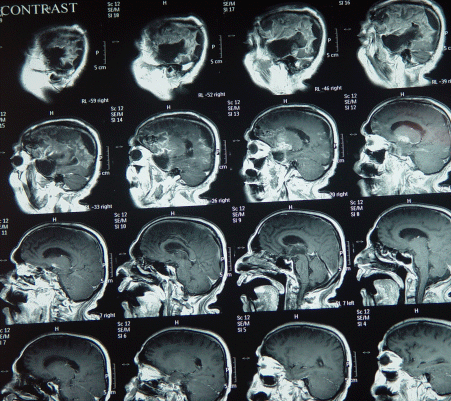

The patient showed steady improvement and the tracheostomy was removed 15-December-2007 and started normal feeding and MRI performed 23-December-2007 showed halt of the aggressive growth of the tumor.

The patient underwent radiotherapy, and MRI done 17-Maech-2008 showed no signs of recurrence, still bedridden and can eat well and some times talking and responding to verbal stimuli.

MRI repeated 18-August-2008  showing of the other left hemisphere and involvement of the brain stem in the right side. with deterioration of his condition.

MRI done 04-December-2008 showing enlargement of the right sylvian mass location and down to the vermis. He is completely bedridden and to my knowledge he died 3-4 months later.